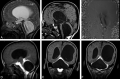

CE-MRC has been in use for the past 15 years and was reported to be a useful method in the evaluation of CSF disorders and hydrocephalus. The use of CE-MRC in conjunction with other MR imaging techniques has been shown to be effective in selected cases for the evaluation of several disorders of cerebrospinal system. CE-MRC has certain advantages over other cisternographic studies with fewer side effects if performed properly. Although intrathecal Gd administration is not widely accepted yet, several recent studies have reported the safety of small-dose intrathecal gadolinium injection. In this review, we describe CE-MRC and review recent applications in several clinical conditions.